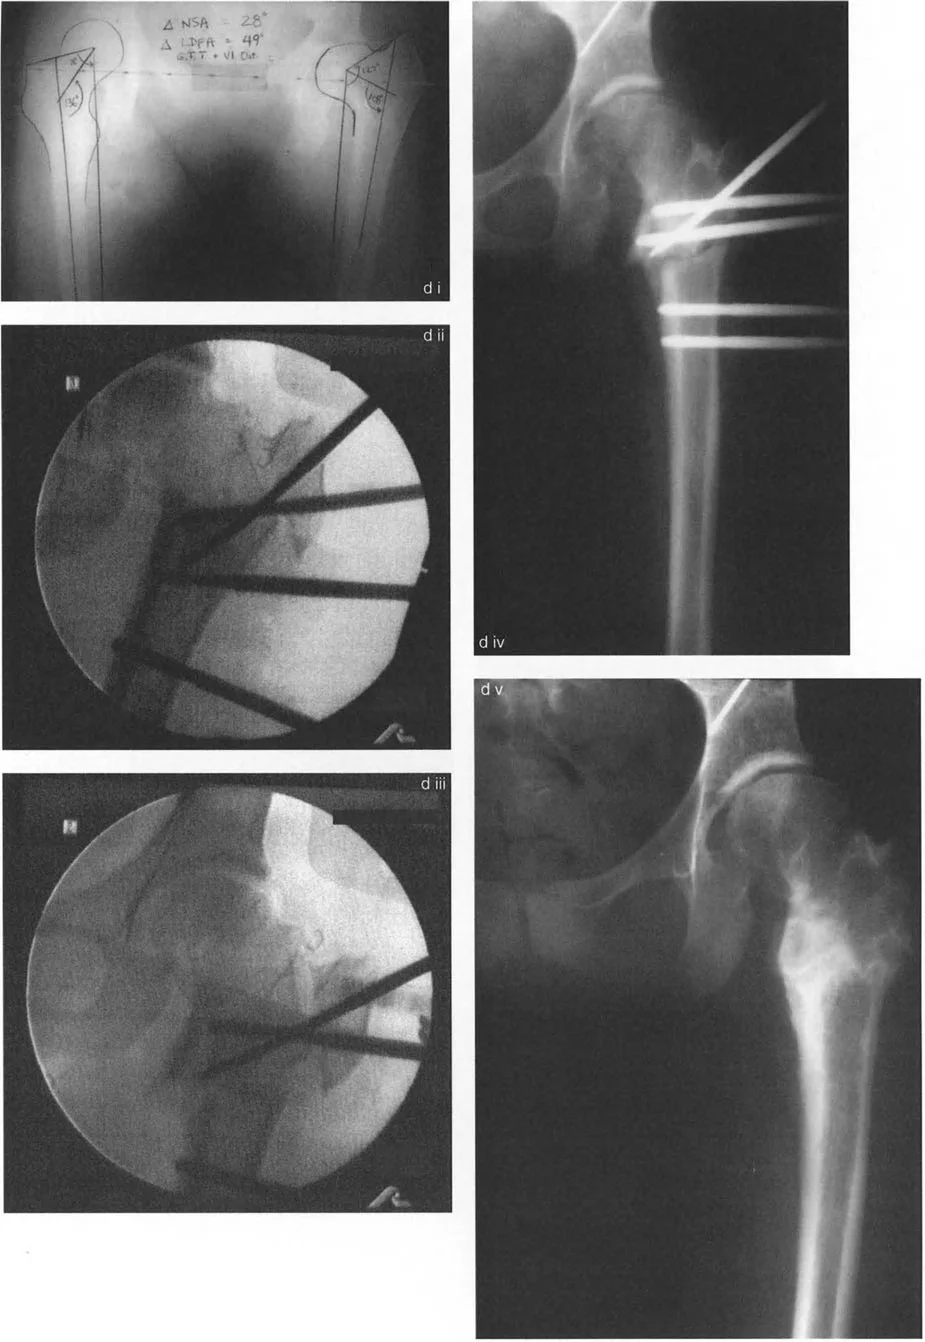

- تُستخدم هذه الأشعة لقياس المحور الميكانيكي، وزوايا المفاصل (mLDFA، MPTA)، وتحديد الموقع الدقيق لمركز دوران الزاوية (CORA). هذه القياسات الدقيقة هي حجر الزاوية في التخطيط الجراحي.

- باستخدام برامج حاسوبية متخصصة، يقوم الأستاذ الدكتور محمد هطيف بتحميل صور الأشعة السينية والقياسات لتحديد الخطة الجراحية المثلى بدقة متناهية.

- يتضمن ذلك تحديد مستوى قطع العظم، وحجم التصحيح المطلوب، ونوع الأجهزة التي ستُستخدم. هذا التخطيط الافتراضي يقلل من المفاجآت أثناء الجراحة ويزيد من دقة النتائج.

قواعد بالي لقطع العظم

تُعد مبادئ الدكتور درور بالي (Dr. Dror Paley) حجر الزاوية في فهم سلوك العظام عند قطعها وتصحيحها. تبسط هذه القواعد المعقدة كيفية تفاعل أجزاء العظم عند التلاعب بها حول محور معين.

القاعدة الأولى: التصحيح المثالي للزاوية:

- عندما يتم إجراء قطع العظم ومحور التصحيح (النقطة التي يتم حولها ثني العظم) في نفس مستوى مركز دوران الزاوية (CORA)، يحدث تصحيح زاوي نقي.

- في هذه الحالة، تعود الخطوط الميكانيكية للجزء القريب والبعيد من العظم إلى محاذاة مثالية دون أي انزياح جانبي (إزاحة) ثانوي. هذا هو السيناريو المثالي للتشوهات البسيطة في منطقة الميتافيز (نهاية العظم القريبة من المفصل).

القاعدة الثانية: التصحيح الزاوي مع انزياح العظم:

- عندما يتم إجراء قطع العظم في مستوى مختلف عن مركز دوران الزاوية (CORA)، ولكن محور التصحيح يظل في الـ CORA، فإن الخطوط الميكانيكية للطرف ستعود إلى محاذاة مثالية.

- ومع ذلك، ستخضع نهايات العظم عند موقع قطع العظم لانزياح جانبي (ترجمة) بالإضافة إلى التصحيح الزاوي. هذا ما يُعرف بعملية "قطع العظم الزاوي-الترجمي" (Angulation-Translation - a-t Osteotomy).

القاعدة الثالثة: انزياح ثانوي غير مرغوب فيه:

- عندما يتم إجراء قطع العظم ومحور التصحيح كلاهما في مستوى مختلف عن مركز دوران الزاوية (CORA)، سيحدث انزياح جانبي ثانوي غير مرغوب فيه.

- في هذه الحالة، ستبقى الخطوط الميكانيكية متوازية ولكنها لن تكون متطابقة، مما يؤدي إلى استمرار انحراف المحور الميكانيكي (MAD) على الرغم من تصحيح التشوه الزاوي الظاهري. هذا الوضع غير مرغوب فيه ويجب تجنبه.

عملية قطع العظم الزاوي-الترجمي (a-t osteotomy) هي تطبيق سريري للقاعدة الثانية لبالي، حيث يتم إزاحة أجزاء العظم عمدًا لتحقيق محاذاة مثالية للمحور الميكانيكي.